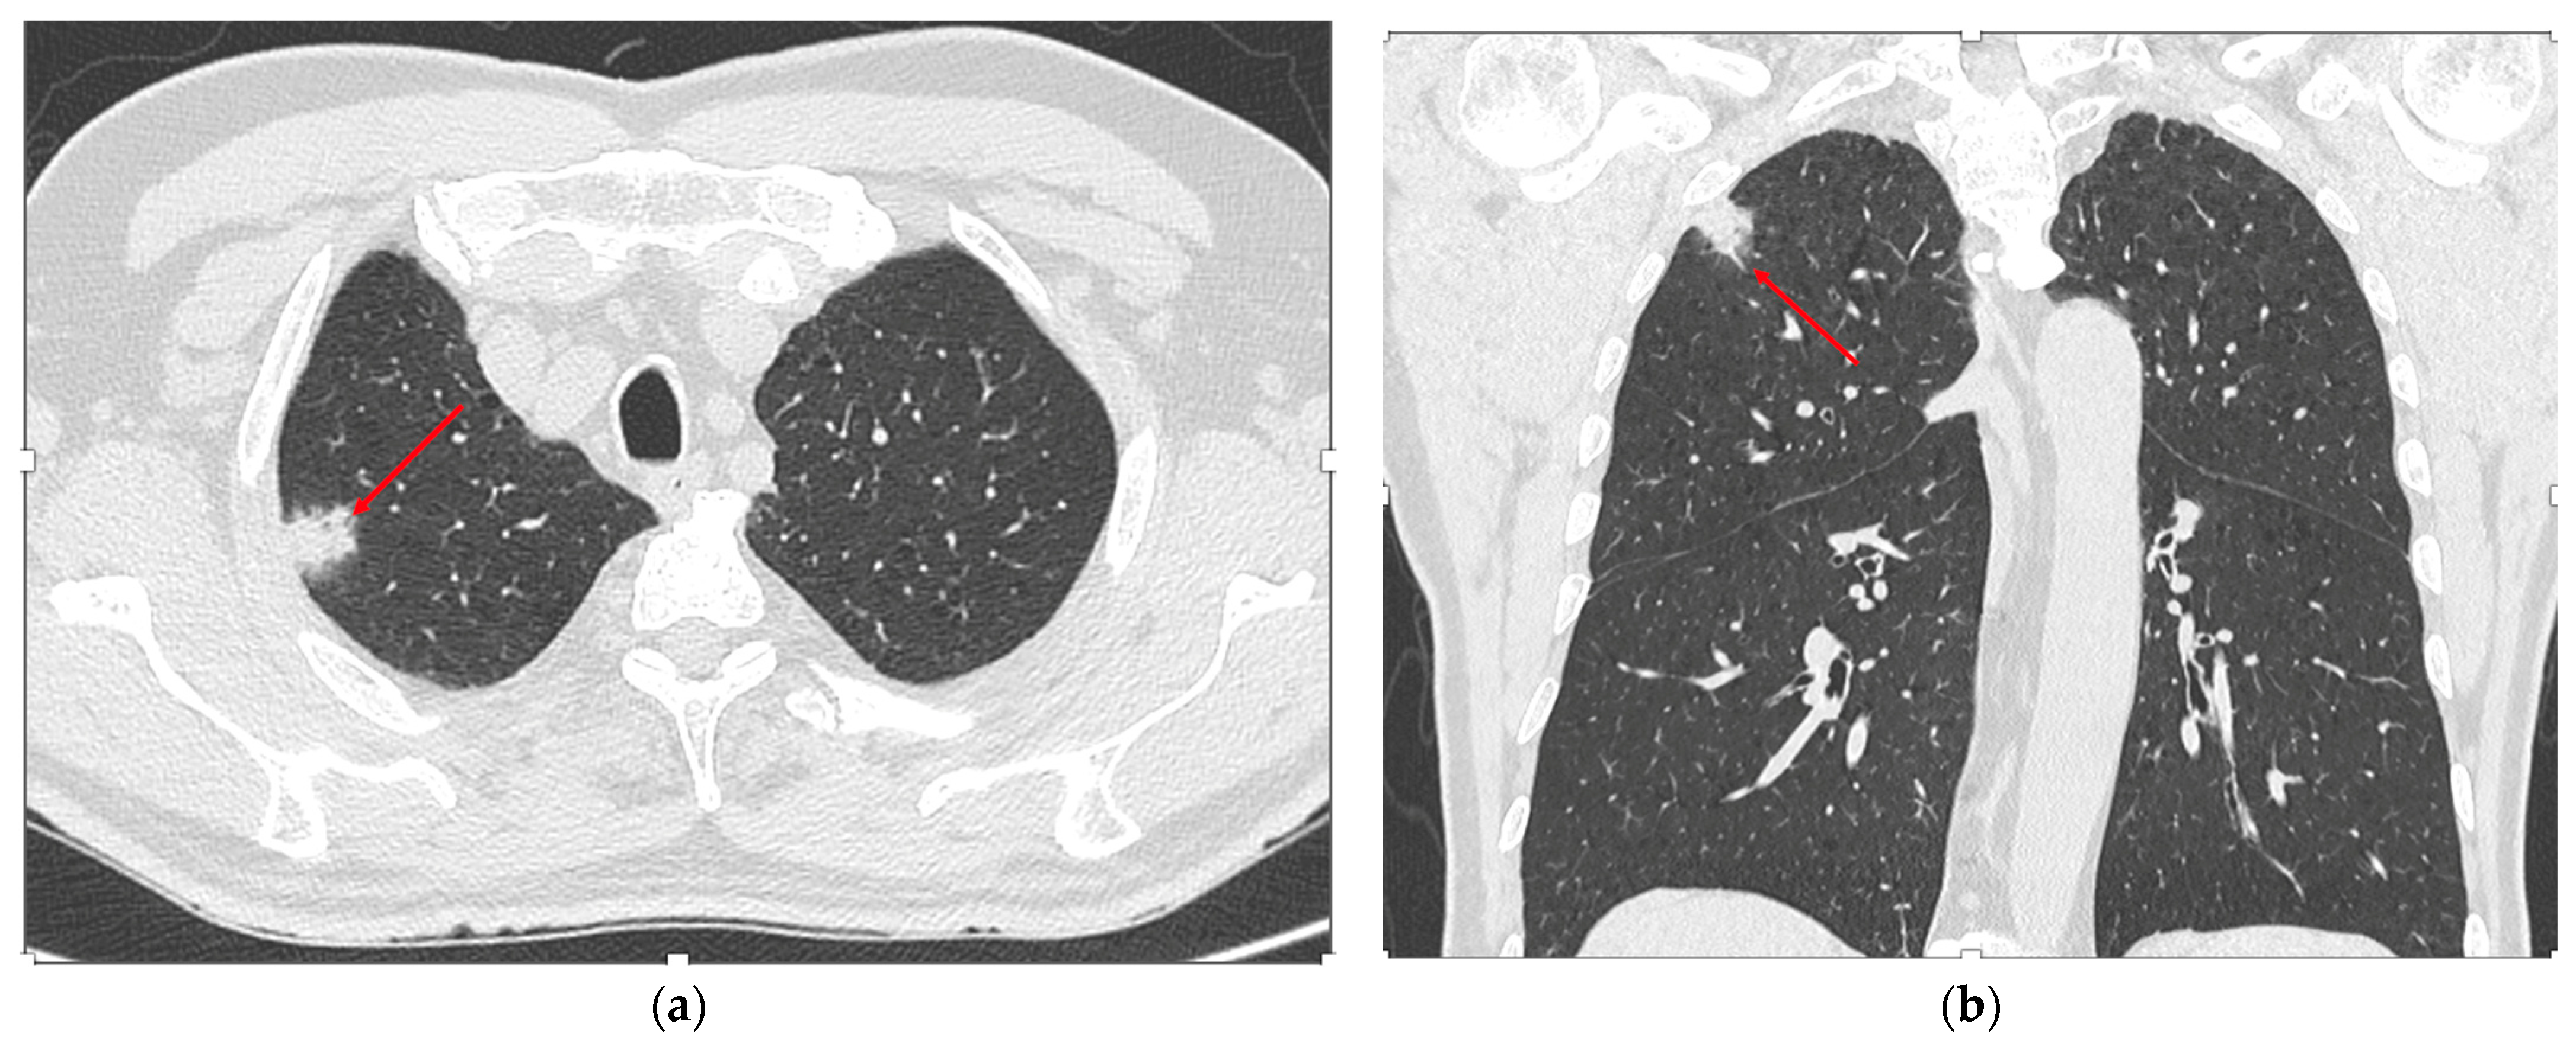

2.3. Imaging Analysis